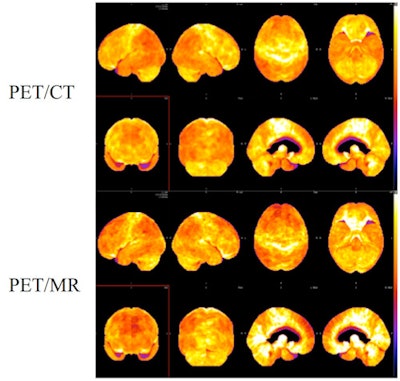

CHICAGO - Simultaneous PET/MRI can produce diagnostic-quality brain scans and interpretation results that compare favorably with PET/CT in patients with clinically suspected dementia, according to a study presented on Thursday at RSNA 2013.

Preliminary findings showed good concordance of diagnosis and severity of findings between PET/MRI and PET/CT when evaluated by two experienced nuclear medicine physicians, the researchers found.

In the study, 19 patients with clinically suspected dementia underwent a 15-minute PET/CT brain scan (Biograph mCT, Siemens Healthcare) 45 minutes after injection of 10 mCi of FDG. Simultaneous PET/MRI (Biograph mMR, Siemens) followed approximately 90 minutes after FDG injection.

When compared with PET/CT, PET/MRI interpretations yielded 84% (16/19) intrareader agreement in diagnosis. Also, 95% (18/19) of severity scores varied by one point or less between the two readers.